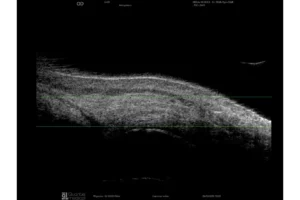

Quantel Medical heeft een sprong voorwaarts gemaakt met de nieuwe technologie met 5 ringen op een 20 MHz-sonde. Het principe is om om en om ultrasone geluidsgolven uit te zenden via 5 concentrische transducers in dezelfde sonde. Deze technologie:

- Verhoogt het focusgebied

- Vermindert de laterale resolutie van 250 naar 200 µm, oftewel met 25%

- Behoudt een hoge axiale resolutie

Het volledige oog is nu zichtbaar met een uitstekend detailniveau.

Verlengde scherptediepte van 70%

De ringtechnologie verdubbelt praktisch de scherptediepte. De 20 MHz-ringvormige sonde heeft een verlengde scherptediepte van 70%, waardoor het mogelijk is om pathologieën van het glasvocht, het netvlies en verder tegelijkertijd te observeren zonder concessies te doen aan de beeldresolutie.